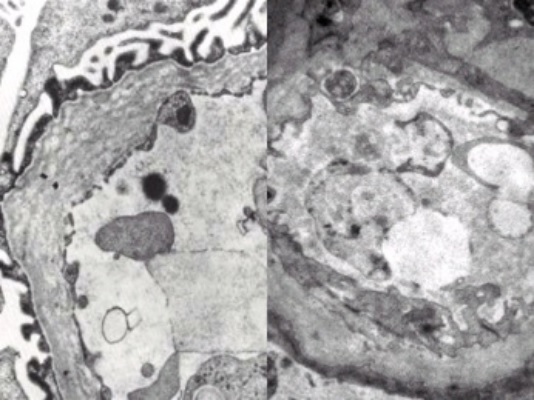

部分超微病理电镜图示例:

图2 神经肌肉疾病